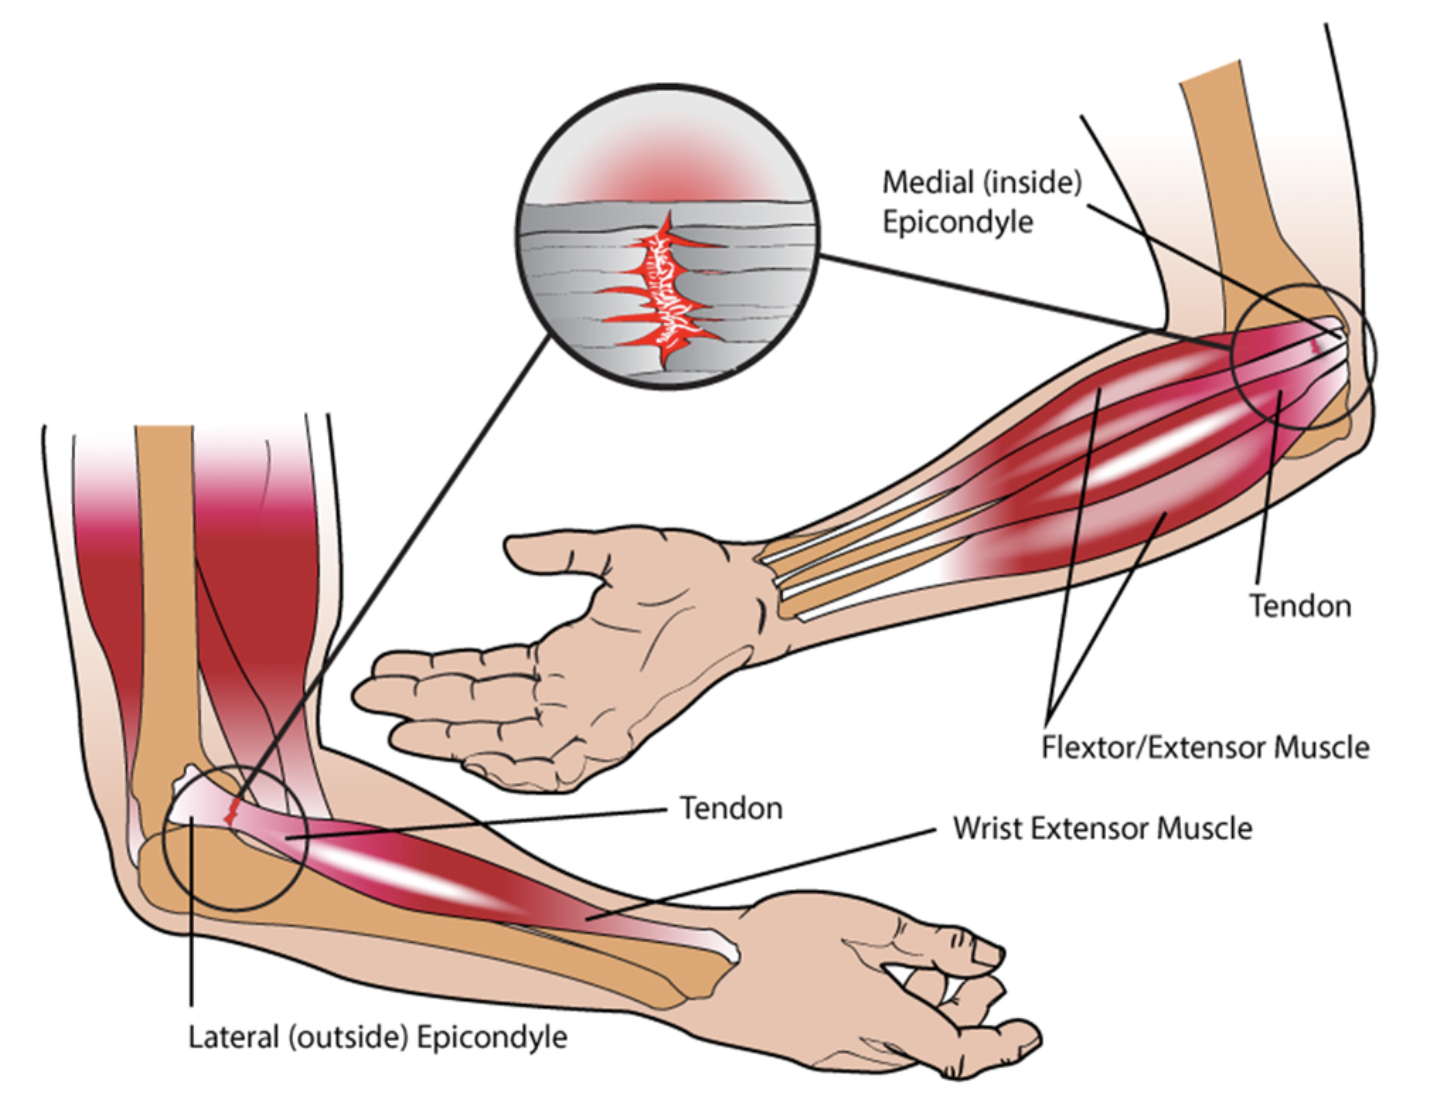

网球肘(又称肘外侧肌腱病)的干预措施比较

参考文献:Lowdon, H., Chong, HH, Dhingra, M., Gomaa, A.-R., Teece, L., Booth, S., Watts, AC, & Singh, HP (2024)。干预措施比较...